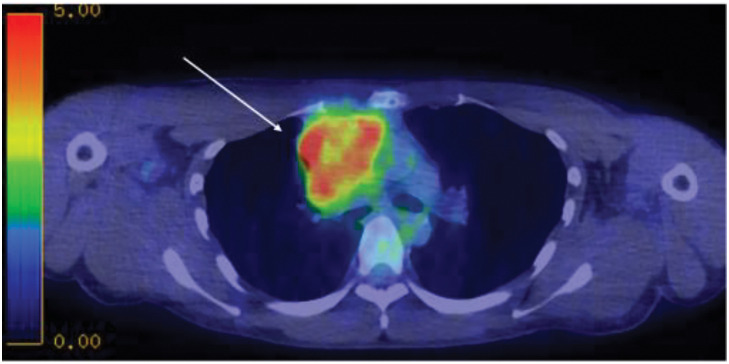

Case presentation: The patient was a 25-year-old man who had been experiencing labored breathing when leaning forward for the past month. Physical examination revealed distended jugular veins and neck edema. Chest computed tomography revealed an irregular mass measuring 80 mm in the anterior mediastinum, suggesting invasion of the superior vena cava. Additionally, fluorodeoxyglucose-positron emission tomography showed high accumulation in the same area, with a maximum standardized uptake value of 11.3. A tumor biopsy was performed under thoracoscopic guidance for definitive diagnosis. Histopathological examination of the resected specimen revealed a seminoma with granulomatous changes. Based on these findings, a diagnosis of anterior mediastinal seminoma with superior vena cava syndrome was made. It was classified as having a good prognosis, and the patient received three courses of induction chemotherapy with etoposide, cisplatin, and ifosfamide. Complete remission was achieved. Since then, the patient has been monitored every 3 months, with no recurrence or metastasis observed for approximately 2 years.